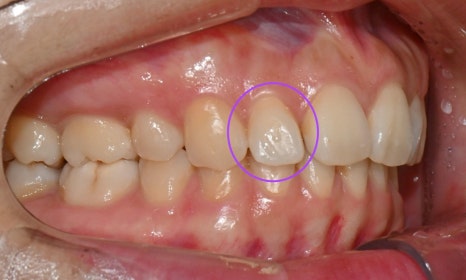

본 환자는 예전에 발치교정을 했는데 과개교합 때문에 위 치아 유지장치 관리가 잘 되지 않아 앞니가 살짝 벌어지고 치아 하나가 튀어나온 것이 신경이 쓰인다는 주소로 병원에 내원하셨습니다. 과개교합 때문에 위아래 앞니가 서로 부딪혀서 유지장치가 떨어졌고, 유지장치 관리가 잘 안되니 앞니 사이가 점점 벌어지고 오른쪽 앞니가 튀어나온다고 하셨습니다.

장치 교정을 할 경우 사회생활을 하는데 비심미적이고, 기간이 오래 걸려서 빠른 시일 안에 교정 치료를 원하셔서 위 앞니만 인비절라인 익스프레스로 진행하길 원하셨습니다.